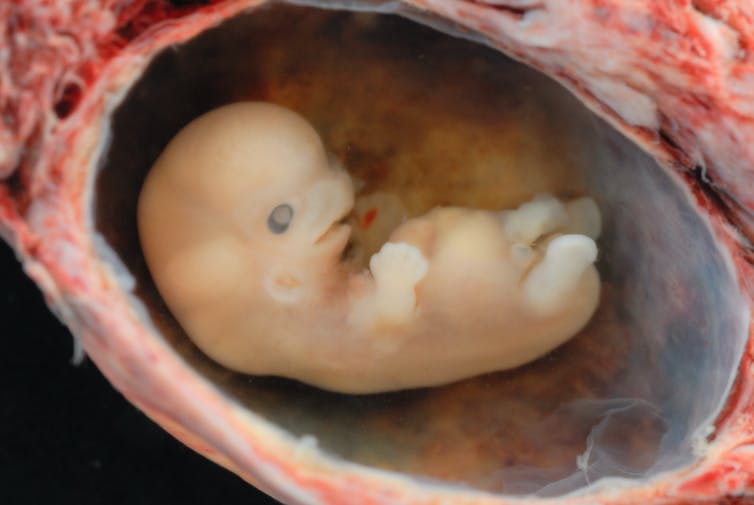

이 단계의 첫 번째 단계는 수정란이 완전한 인간 유전 물질로 형성될 때 난관에서 수정되는 것이다. 그러나 모든 사람의 몸에 있는 거의 모든 세포는 그 사람의 완전한 DNA 서열을 가지고 있다. 만약 유전 물질만으로도 잠재적인 인간이 될 수 있다면, 우리가 항상 그렇듯이 피부 세포를 흘리는 순간 우리는 잠재적인 인간을 잘라내고 있는 것이다.

두 번째 그럴듯한 단계는 수정 후 약 2주에 발생하는 장배 형성(gasstrulation)**이라고 한다. 그 시점에서 배아는 일란성쌍둥이 또는 세 쌍둥이 또는 그 이상을 형성하는 능력을 잃는다. 따라서 배아는 생물학적 개체가 되지만 반드시 인간 개체는 아니다.

세 번째 가능한 단계는 태아의 뇌에서 인간 특유의 뇌파 패턴이 나타나는 임신 24~27주이다. 이 패턴이 사라지는 것은 인간 사망에 대한 법적 기준의 일부이다. 대칭적으로 말하면, 아마도 그 모습은 인간 생명의 시작을 표시하는 것으로 간주될 수 있다.